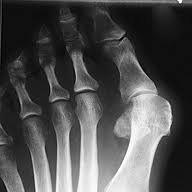

Hallux valgus før og etter operasjon.Hallux valgus er en feilstilling av stortåen (hallux) slik at den vris i retning lilletåen (valgus). Samtidig er stortåens grunnledd delvis ute av ledd og forskjøvet innover mot den andre foten. Typisk finner vi skjevhet i stortåen og sårhet over stortåens grunnledd. Leddet hovner opp og blir svært markert og prominerende på innsiden av foten, og det blir smertefullt og ømt. Forandringene i foten kan gjøre det vanskelig å finne sko som passer godt på foten.

Det anvendes ulike operasjonsmetoder, og det er ikke vist at en bestemt metode er klart bedre enn de andre. I Norge foretrekkes oftest operasjonsmetoden distal chevron osteotomi.

Den vanligste metoden er at stortåens mellomfotsben deles og forskyves (osteotomi) slik at skjevheten rettes opp. Kirurgen lager et brudd i beinet, fjerner en kile av beinet slik at retningen på tåen endres. Dette bruddet må gro. Du må gå med gips på foten i 6-8 uker eller en ortose eller spesialsko. Kontroll avtales på poliklinikken på dette tidspunkt. På kontrollen fjernes gipsen, og stingene etter operasjonen blir tatt.